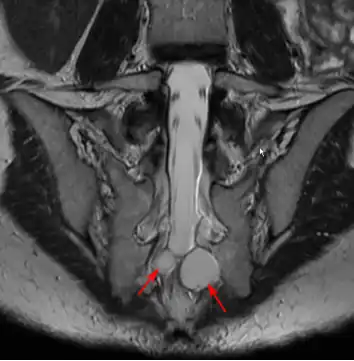

MRI image showing a Tarlov cyst -

MRI sagittal image of sacral and dorso-lumbar perineural cysts.

MRI

MRI, or Magnetic Resonance Imaging, is considered the imaging study of choice in identifying Tarlov cysts. MRI provides better resolution of tissue density, absence of bone interference, multiplanar capabilities, and is noninvasive. Plain films may show bony erosion of the spinal canal or of the sacral foramina. On MRI pictures, the signal is the same as the CSF one.